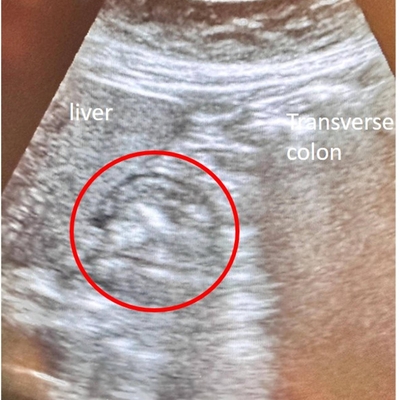

Click on an image below to view more info.